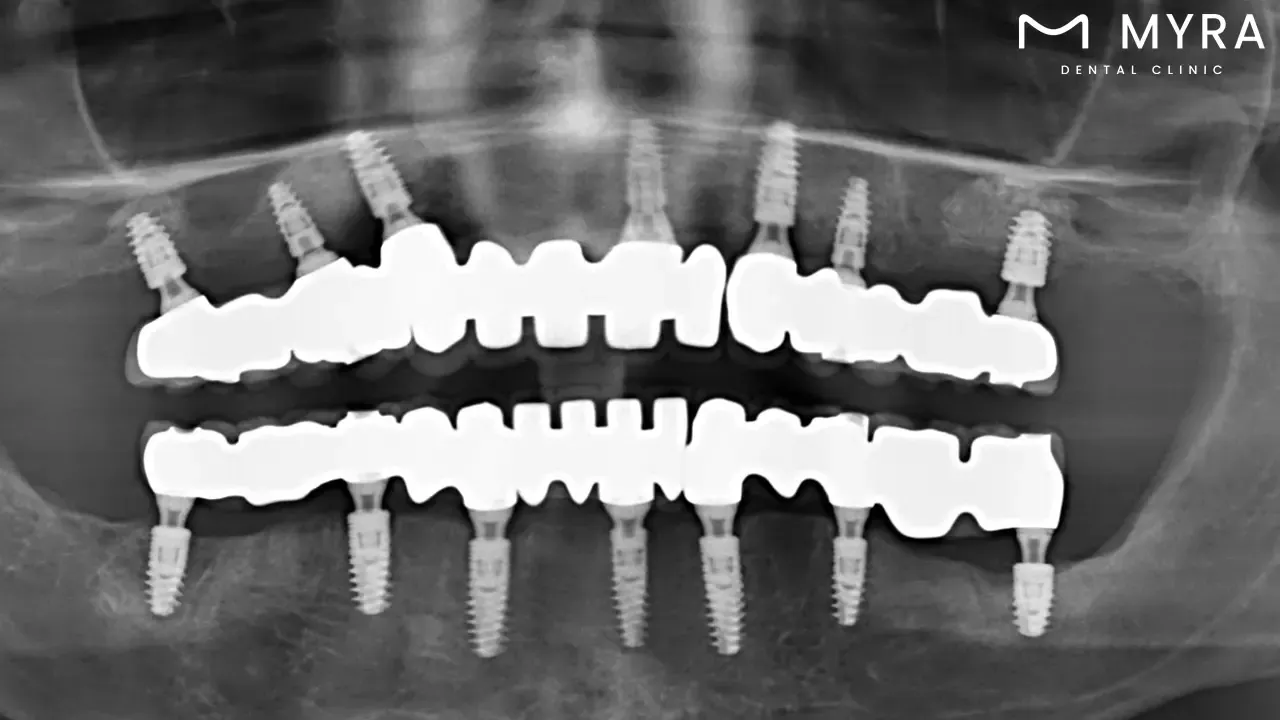

Dental implants are prosthetic teeth or other dental prostheses that are surgically inserted into the jawbone to serve as artificial tooth roots made of biocompatible materials, such as titanium. The implants provide a solid basis for an array of dental restorations, such as single crowns, bridges, and overdentures. The durability and functionality of dental implants depend heavily on proper care and maintenance.

A dental implant is a form of restorative dentistry involving the surgical implantation of artificial tooth roots into the mandible. These titanium posts are designed to serve as anchors for dental remedies and to mimic the look and operation of inherent teeth. Dental implants deliver a stable foundation for dental prostheses including crowns, bridges, and dentures by integrating with the mandible through osseointegration.